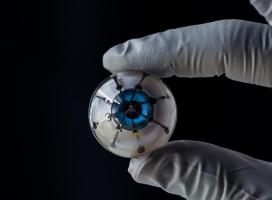

Actualité publiée le 12/04/2019MÉDECINE RÉGÉNÉRATIVE : Le premier œil bionique en 3D

Actualité publiée le 29/09/2018